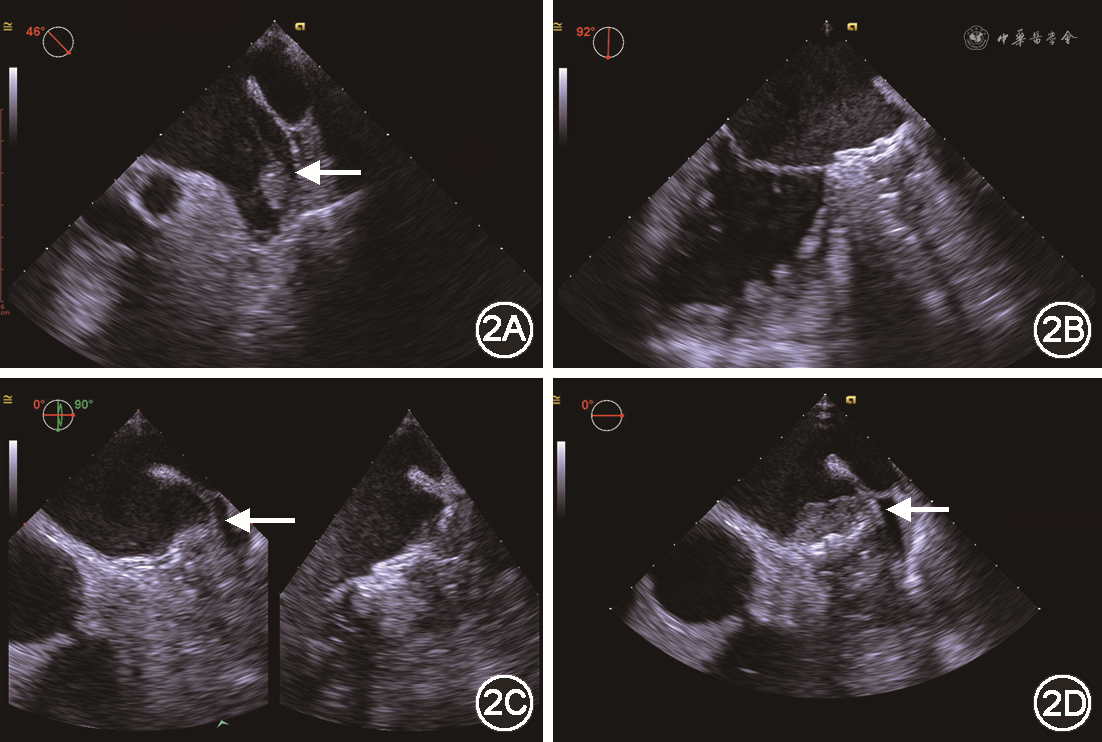

患者男,83岁,主因“反复心悸10余年,再发2 d伴头晕”于2019年8月14日入院。患者有长程持续性心房颤动(房颤)病史10余年,未曾服用抗凝药物。2019年7月7日患者因胸闷心悸伴气短就诊,心电图示房颤伴快速心室率。既往有反复脑梗死、冠心病、高血压、糖尿病、肾功能不全病史。实验室检验结果:空腹血糖9.00 mmol/L(参考值4.10~5.90 mmol/L),尿素氮13.00 mmol/L(参考值2.50~6.10 mmol/L),肌酐159 μmol/L(参考值46~92 μmol/L),N末端B型利钠肽原1 514 ng/L(参考值0~125 ng/L),甲状腺功能正常。经胸超声心动图:左心房前后径48 mm,上下径80 mm,左右径50 mm,轻度二尖瓣反流,主动脉瓣钙化伴轻度反流,左心室射血分数65%。头颅CT平扫:脑内多发腔隙性梗死(部分陈旧)及缺血灶,右侧颞枕顶软化灶;老年脑改变。心脏CT血管成像(CTA):左心耳底部局部充盈缺损,提示左心耳血栓形成(图1)。予华法林2.5 mg(每日1次)口服,调整国际标准化比值(INR)2~3。患者未定期复查INR,后因反复胸闷心悸不适,于8月14日再次入院。经食道超声心动图(TEE):左右心房血液瘀滞,左心耳更明显,并见20.0 mm×7.0 mm低回声团,无明显活动度,蒂位于心耳上壁偏前近心耳尖部(图2A)。诊断:长程持续性房颤,纽约心脏病协会(NYHA)心功能Ⅱ级,左心耳血栓,冠心病,高血压,陈旧性脑梗死,2型糖尿病,肾功能不全。CHA2DS2-VASc评分8分,HAS-BLED评分3分。

经讨论决定行左心耳封堵术。经股动脉路径将EZ血栓保护系统H74920100-1900(波科国际医疗贸易上海有限公司)送至左、右侧颈内动脉,房间隔穿刺成功后予以肝素钠监测激活凝血时间(ACT)250~350 s之间。交换送入LAmbre[先健科技(深圳)有限公司]输送外鞘及猪尾造影导管,调整至心耳开口,造影显示左心耳呈菜花形,测左心耳开口直径为30 mm,内口直径为24 mm。输送内鞘抵左心耳口部,选用LAmbre封堵器型号为LT-LAA-2832,于左心房心耳口外打开封堵器固定盘,推送至心耳内锚定,血栓随固定盘推入左心耳底部,然后回撤外鞘,在左心耳开口外打开密封盘。复查左心房造影和TEE,见封堵器位置合适,伞周上缘偏前见约2 mm残余分流;左心房及封堵伞周围未见异常回声,牵拉稳定,对周围结构无影响,缓慢释放封堵器(图2B)。术后予华法林抗凝,初始剂量为1.875 mg(每日1次),调整INR 2~3。左心耳封堵后8周复查TEE,示封堵器位置良好,伞周上缘、上缘偏前均见约1 mm残余分流,密封盘伞面上侧见18.0 mm×6.0 mm低回声团块。抗凝治疗方案改为利伐沙班联合氯吡格雷。左心耳封堵后16周再次复查TEE,示左心房内明显血流瘀滞,密封盘伞面见混合回声团块18.0 mm×2.5 mm,左心房部分稍高回声,伞面部分低回声,考虑血栓机化;密封盘上缘,上缘偏前,及后缘偏下见1.5、1、1 mm残余分流(图2C)。抗凝治疗方案改为阿司匹林联合氯比格雷,密切随诊,患者一般状况稳定。左心耳封堵后12个月复查TEE,提示封堵器位置良好,密封盘伞面9-12点范围见33.0 mm×10.0 mm低回声团块,密封盘上缘、上缘偏前见2处1 mm残余分流(图2D)。予阿司匹林(100 mg,每日1次)联合华法林(2.5 mg,每日1次)长期口服,调整INR 2~3。随诊12个月,患者生活质量可,未发生心脑血管事件。